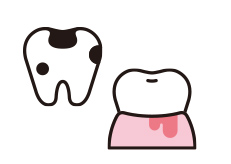

1. なるべく削らない

歯は一度削ってしまうと再生することができません。当院ではむし歯の感染層とそうでない層を精確に見極めて、本当に削る必要のある部分だけを取り除くように努めています。